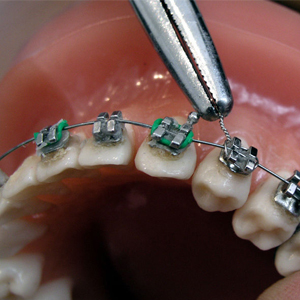

Se encarga de la corrección de las anomalías y mal posiciones dentales con respecto al los maxilares, buscando conseguir alineación y balanceo en el sistema dentó facial por medio de aparatologia fija como son los brakets y/o aparatologÍa removible como son los aparato de ortopedia garantizando funcionalidad y estéticas.

Se encarga de la corrección de las anomalías y mal posiciones dentales con respecto al los maxilares, buscando conseguir alineación y balanceo en el sistema dentó facial por medio de aparatologia fija como son los brakets y/o aparatologÍa removible como son los aparato de ortopedia garantizando funcionalidad y estéticas.

- Ortodoncia Niños

- Ortodoncia Adultos

- Ortodoncia Estética

- Ortodoncia Pre quirúrgica (Anomalías en los maxilares)